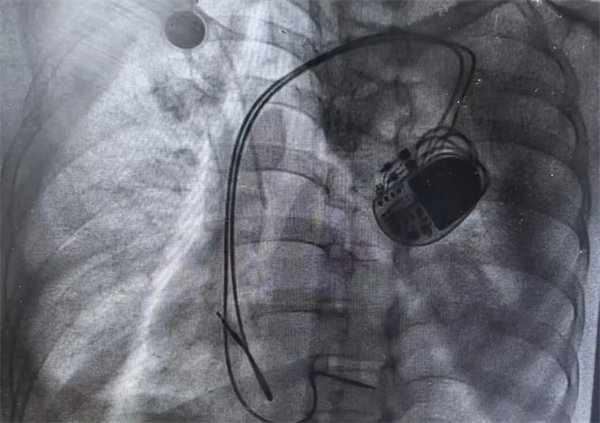

精準植入,重啟生命的“律動”

在充分術前準備和家屬的理解支持下,心血管內一科主任翟向偉副主任醫師、陳萬林副主任醫師及介入導管室團隊為患者實施了雙腔心臟永久性起搏器植入術。通過左側腋靜脈入路,精準、輕柔操作順利植入起搏器。術后經過醫護團隊的精細診治,起搏器囊袋如期愈合,患者可自由活動,生活質量得到有效改善?;颊呒凹覍俾冻隽司眠`的笑容。